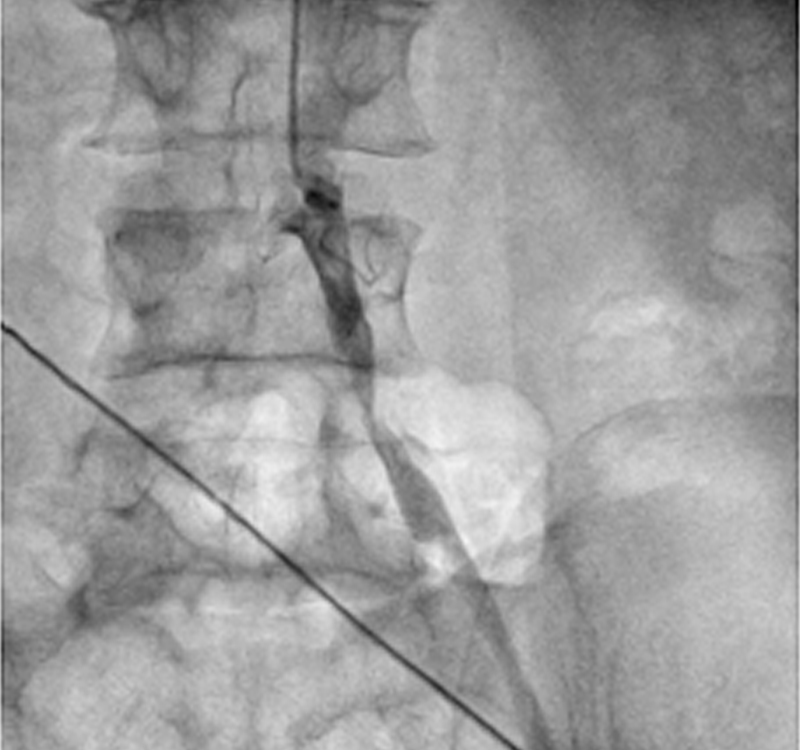

A 56 year old gentleman presented with pain in left leg while walking. He was diabetic and hypertensive. His left lower limb pulse was not palpable. Angiography of his lower limb vessel from radial route was done which showed minor plaque in right side of leg while there was significant blockage (80-90%) in the main vessel of the left leg.

Most of the cardiologist will open the critical blockage in the left leg by inserting catheter from the right leg. Doing these types of cases from radial artery (vessel of hand) is always challenging and one has to have clear idea of approach and familiarity with the hard wire used for performing these types of procedure without any complication.

Critical blockage of left leg was successfully dilated with the balloon and subsequently stent was placed without any complication. Cannula from the arm was immediately removed after the procedure and patient could walk immediately after the procedure. If we do such types of cases by femoral route, patient has to be one bed at least for next 10-12 hours and patient even not allowed to fold the legs for at least 10-12 hours. Patient was discharged successfully next day morning.